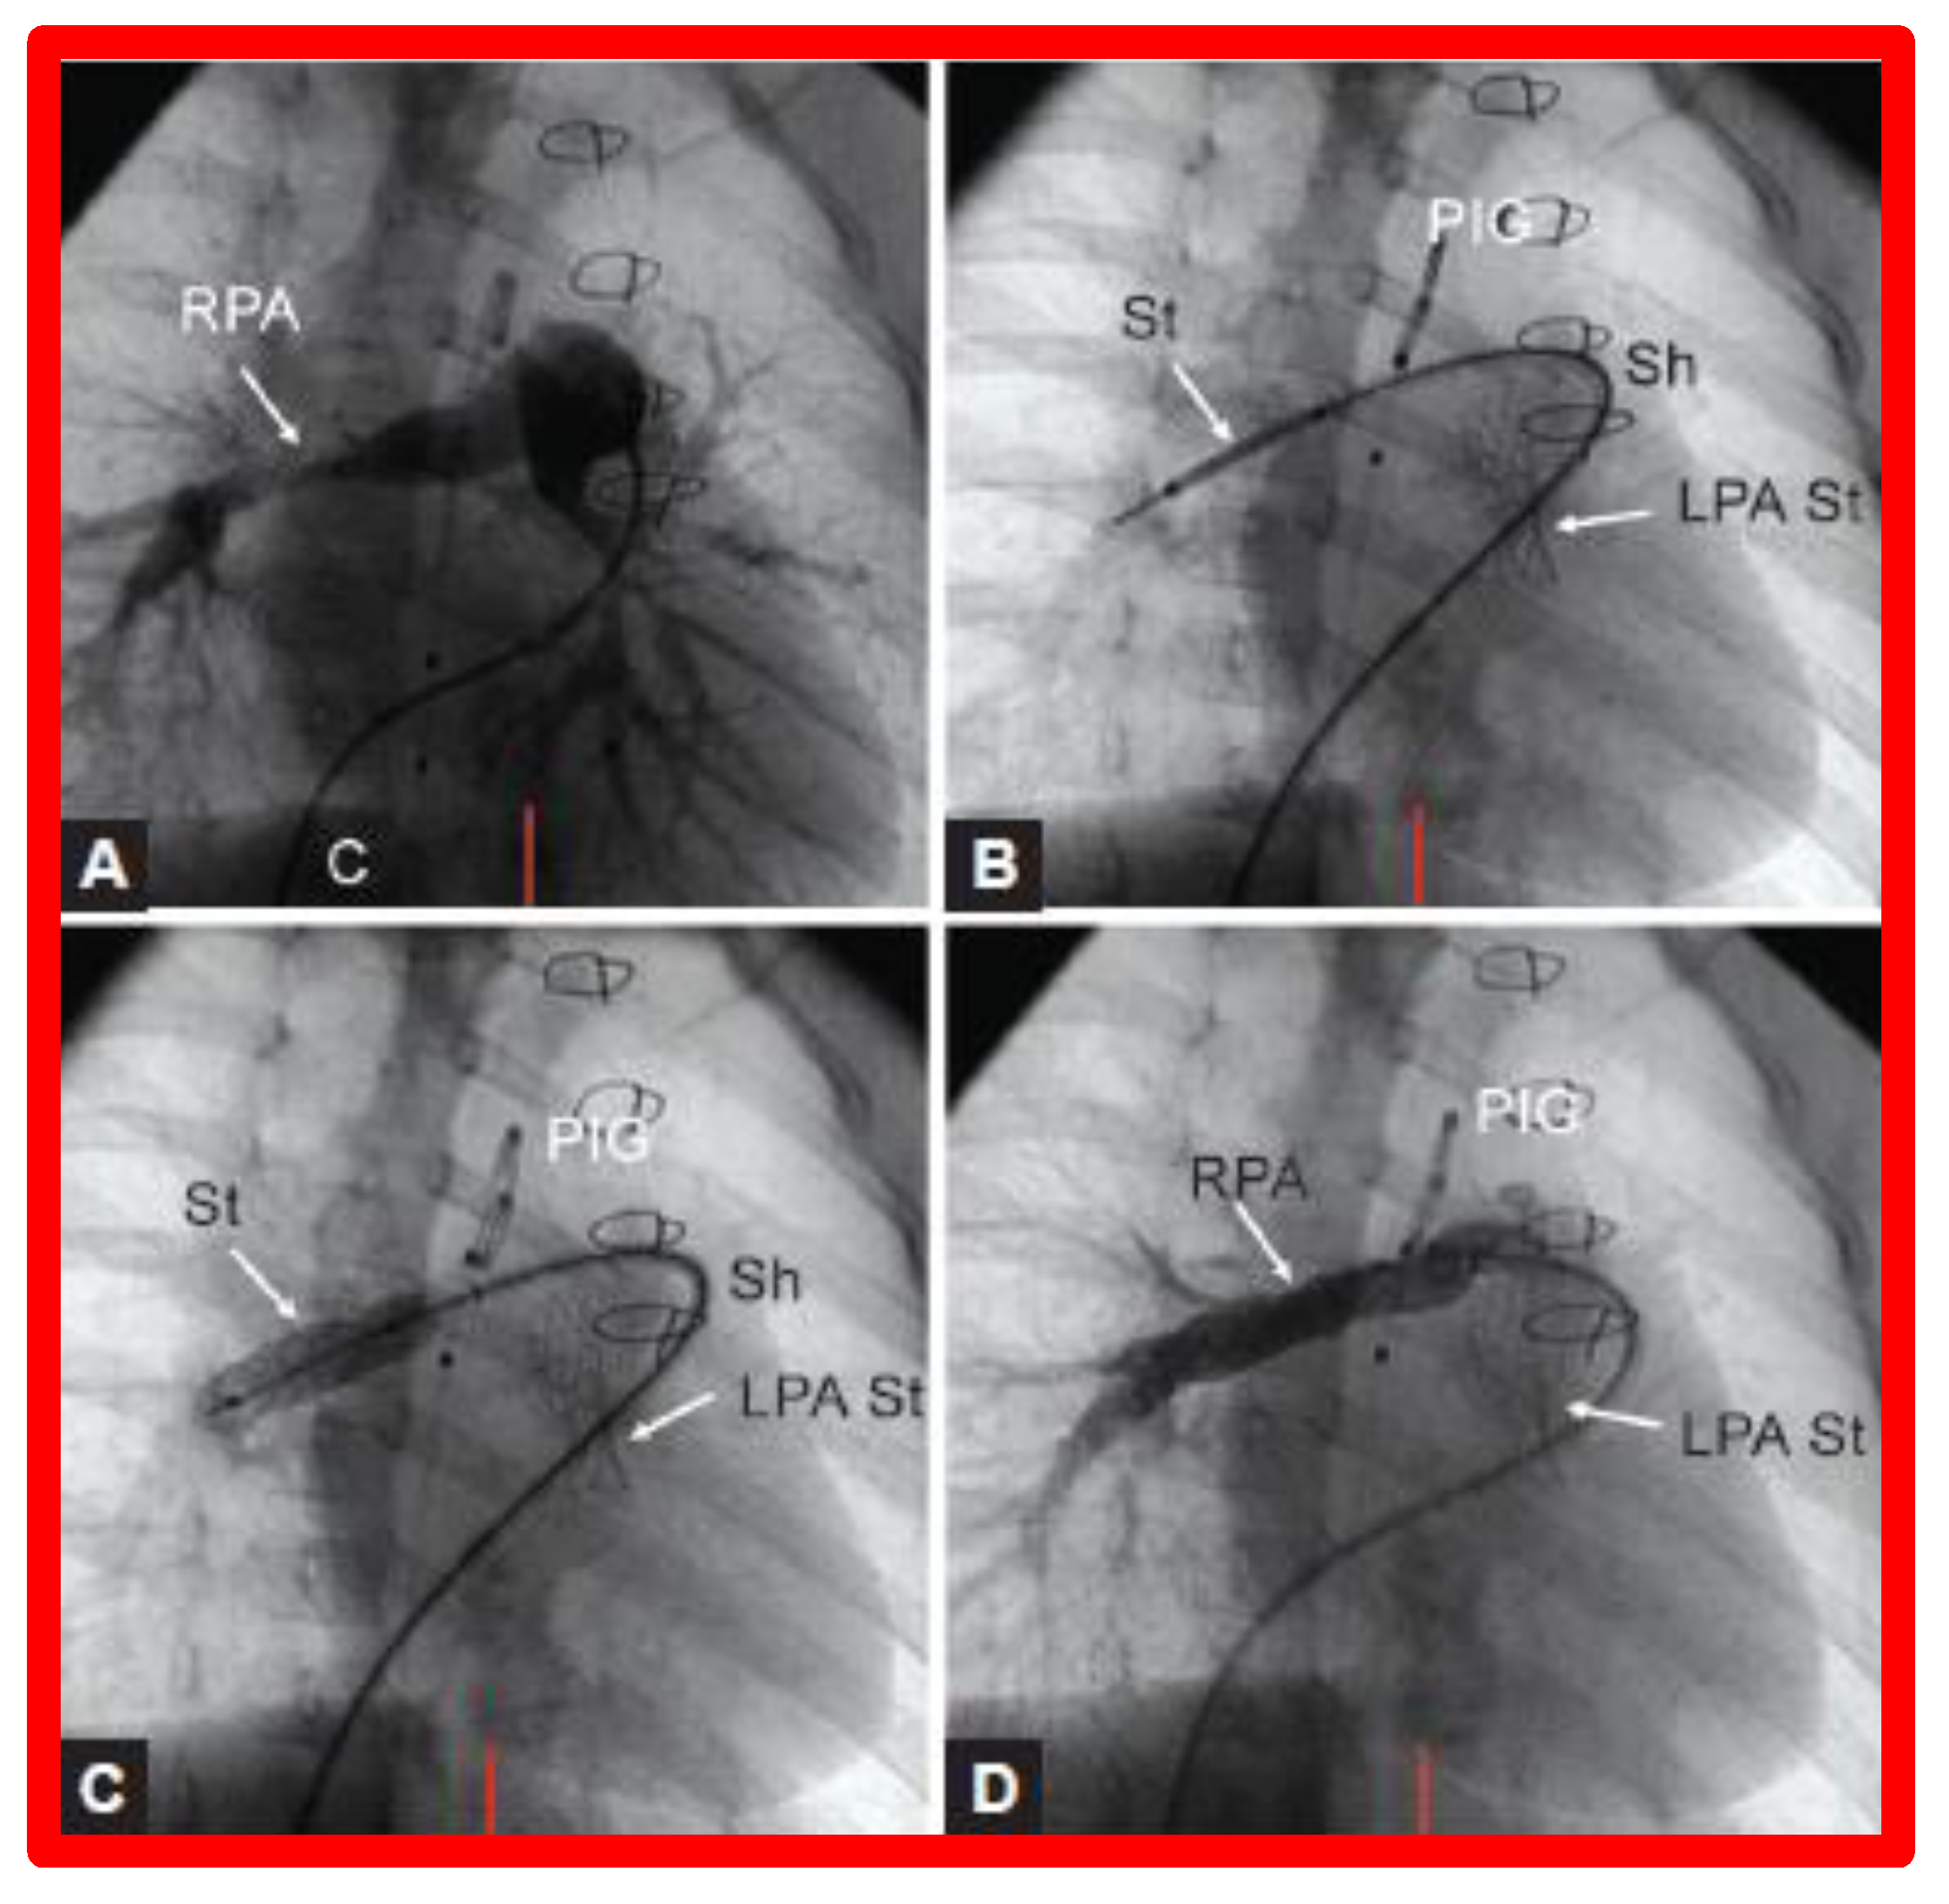

If distortion or stenosis of the branch PAs is detected, balloon angioplasty for discrete obstruction and stents [95,96,97,98,99] for long segment or diffuse narrowing may be indicated (Figure 26). Again, surgery is reserved for situations that can’t be addressed by transcatheter approaches.

Figure 26.

(A). Cineangiographic frames in a 30° right anterior oblique view illustrating long-segment right pulmonary artery (RPA) stenosis (arrow) before implantation of stent (St). The position of the St prior to (B) and following (C) balloon inflation to implant the St are shown. (D). Angiography following St implantation shows improvement. Note trivial residual narrowing (top arrow) in (D). C, catheter; LPA St, left pulmonary artery stent implanted just prior to RPA stent implantation. Sh, sheath; PIG, pigtail catheter. Reproduced from Reference [98].